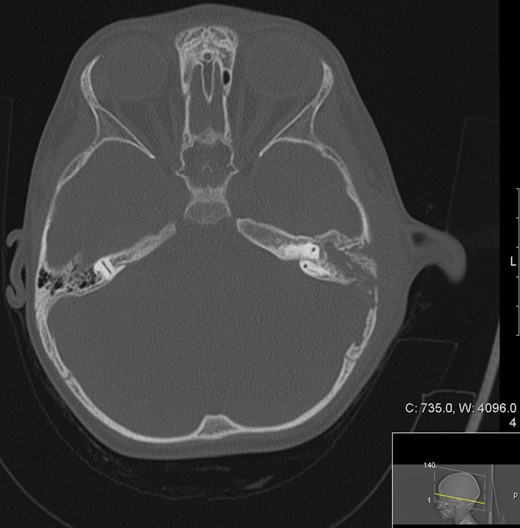

A CT scan of the patient at this point showed mastoiditis, a subperiosteal abscess and extradural abscess with extensive bony defects (Figs 1 and 2). The patient was initially started on IV ceftriaxone and metronidazole. Upon discussion with ENT specialists he underwent a left sided mastoid exploration and drainage of the extradural and peri sigmoid sinus collection on Day 2 of his admission. Surgical exploration found a large parietal subperiosteal abscess with bony defects and granulation tissue connecting with an extradural abscess. Histological diagnosis showed evidence of granulomatous osteomyelitis due to necrotizing granulomatous inflammation. Initial Zeihl-Neelson and Wade Fire stains for acid fast bacilli in tissue culture were negative.

Transverse computer tomography with contrast (angiography), showing the extent of the extradural abscess (black asterisk). L = Left; R = Right. It shows that the left extracranial soft tissue abscess communicates freely through the parietal skull vault defect with the large intracranial extradural abscess, which spans the left tentorial leaflet.